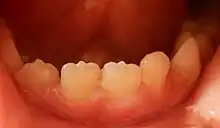

A mamelon (from French mamelon, "nipple") is one of three rounded protuberances which are present on the cutting edge of an incisor tooth when it first erupts through the gum. Mamelons' appearance can be smoothed by a dentist if they have not been worn down naturally by biting and eating foods.[1] Mamelons are present on permanent central and lateral incisors. Mamelons are easiest to observe on the maxillary central incisors, and appear as three small prominences on the incisal edge of the tooth. Mamelons are ordinarily of no clinical importance. Usually they are worn off early in the life of the tooth.

Mamelons on the lower central and lateral right incisors of a seven-year-old boy